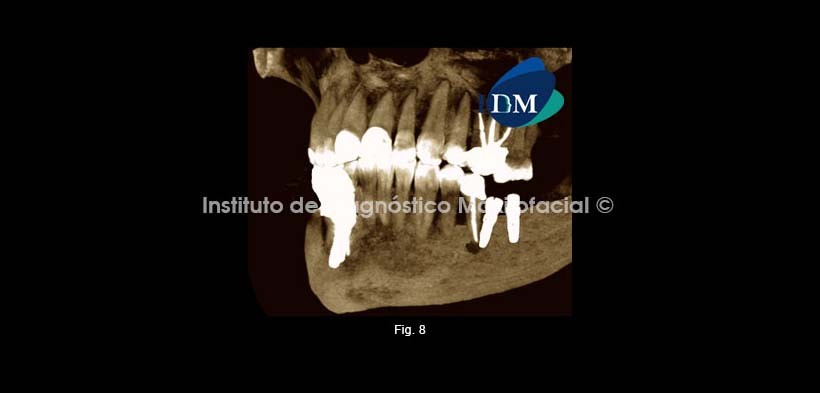

Se procedió a la evaluación con tomografía computarizada de Haz Cónico.

A la evaluación del cuadrante III en mención se pudo observar a nivel de la pieza 3.6 un implante en falsa vía con compromiso de la tabla ósea lingual, sin afectación del conducto dentario, se hizo la evaluación de todos los implantes dentales encontrándose en aparente óseo integración sin afectación de corticales y conservación del conducto dentario. (Fig. 2,3,4,5,6)